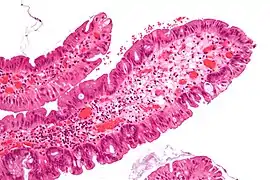

Traditional serrated adenoma. H&E stain.

Micrograph of a tubular adenoma, the most common type of dysplastic polyp in the colon

Micrograph of a tubular adenoma – dysplastic epithelium (dark purple) on left of image; normal epithelium (blue) on right. H&E stain.